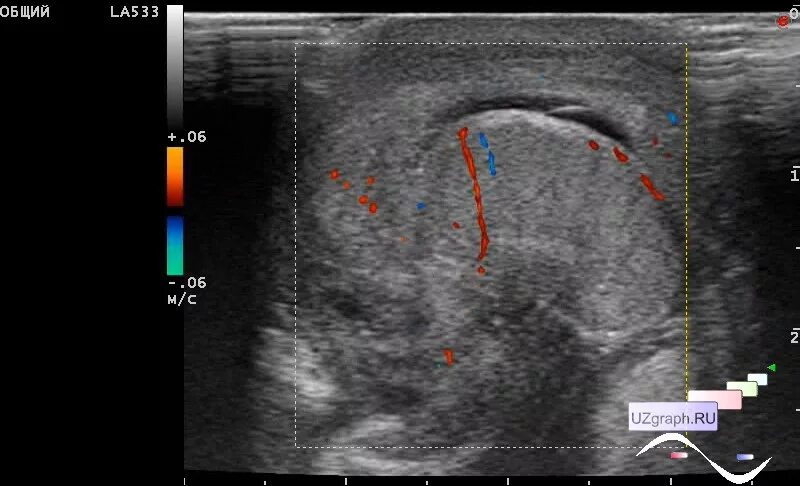

Некроз гидатиды морганьи